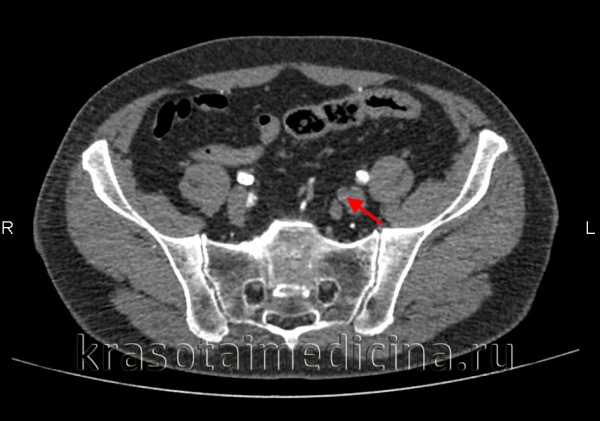

После выполненной реваскуляризации коронарного русла, больному выполнена ангиография артерий нижних конечностей тем же доступом. На ангиограммах: окклюзия ОБА на уровне бифуркации, окклюзия проксимальных частей ГБА и ПБА. (рис. 4) Подколенная артерия (ПкА) проходима, артерии голени визуализируются слабо.

Рис. 4. Ангиограмма ОБА,

ГБА, ПКА слева (LAO 30 0 )